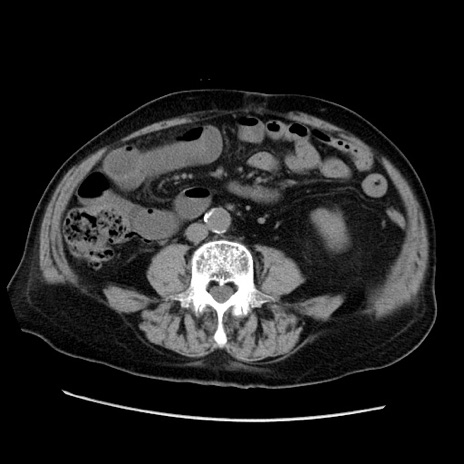

症例21(横断像)

【症例】70歳代男性

【主訴】腹痛

【現病歴】肝硬変・肝細胞癌にてかかりつけの方。約9時間前に食後より腹痛出現。症状が徐々に増悪し、嘔吐出現したため来院。

【既往歴】肝硬変、肝細胞癌(RFA、TACE後)

【身体所見】意識清明、表情苦悶様、BT 36℃、BP 129/78mmHg、P 88bpm、SpO2 97%(RA)、右上腹部から心窩部にかけて圧痛あり、反跳痛なし、筋性防御あり。

【データ】WBC 5800、CRP 0.16